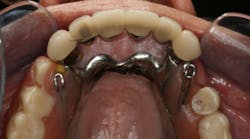

This clinical case began with a frustrated 75-year-old patient, who, after many years of failed attempts to repair the functional problem, came to the realization that a different solution was in order. The existing problem of an upper removable precision attachment partial denture was addressed first. The issue at hand was that the partial denture was perforated at the precision attachments, with the upper left side being more significant compared to the right side (figures 1–5). As a result, retention was adequate on the right side, but limited on the left. The patient was also concerned about esthetics, but needed a solution that kept a restricted budget in mind.

Dentition: Upper anterior splinted crowns had open margins and caries. Radiographs confirm decay, along with open margins (figures 6–11). Lower incisal anterior wear noted (figure 2).